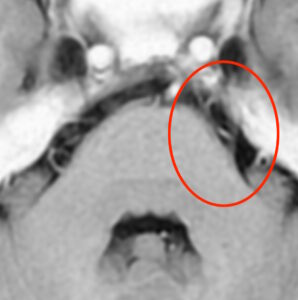

MRIで三叉神経が脳に入る部分を撮像しました。

三叉神経は脳幹という場所に入りますが、斜めに絡まっている血管が見られています。

左の三叉神経の根元の部分に、左の上小脳動脈という血管が接触しています。血管の圧迫による三叉神経痛と診断しました。